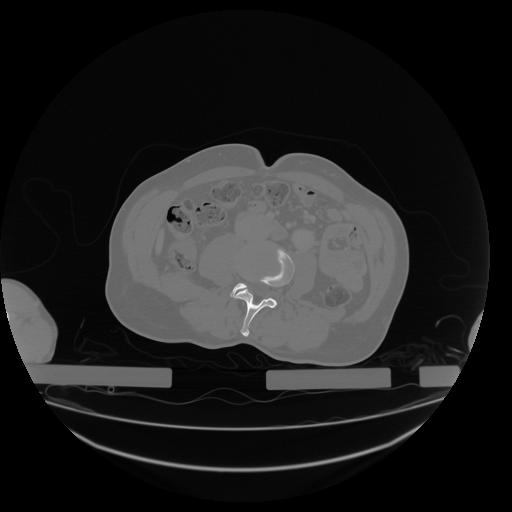

34 CUERPO,CE,Vol,1.0,CUERPO,,